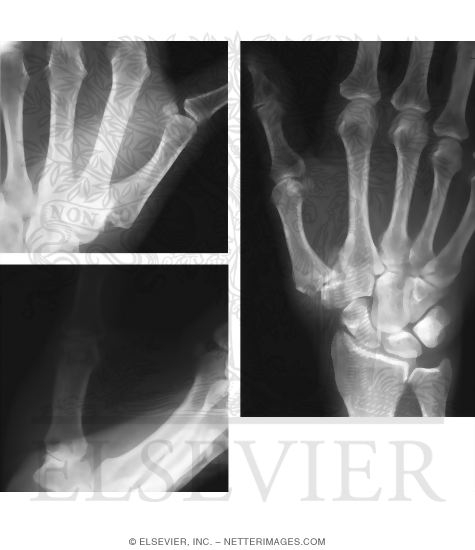

Osteoarthritis of Thumb Carpometacarpal Joint